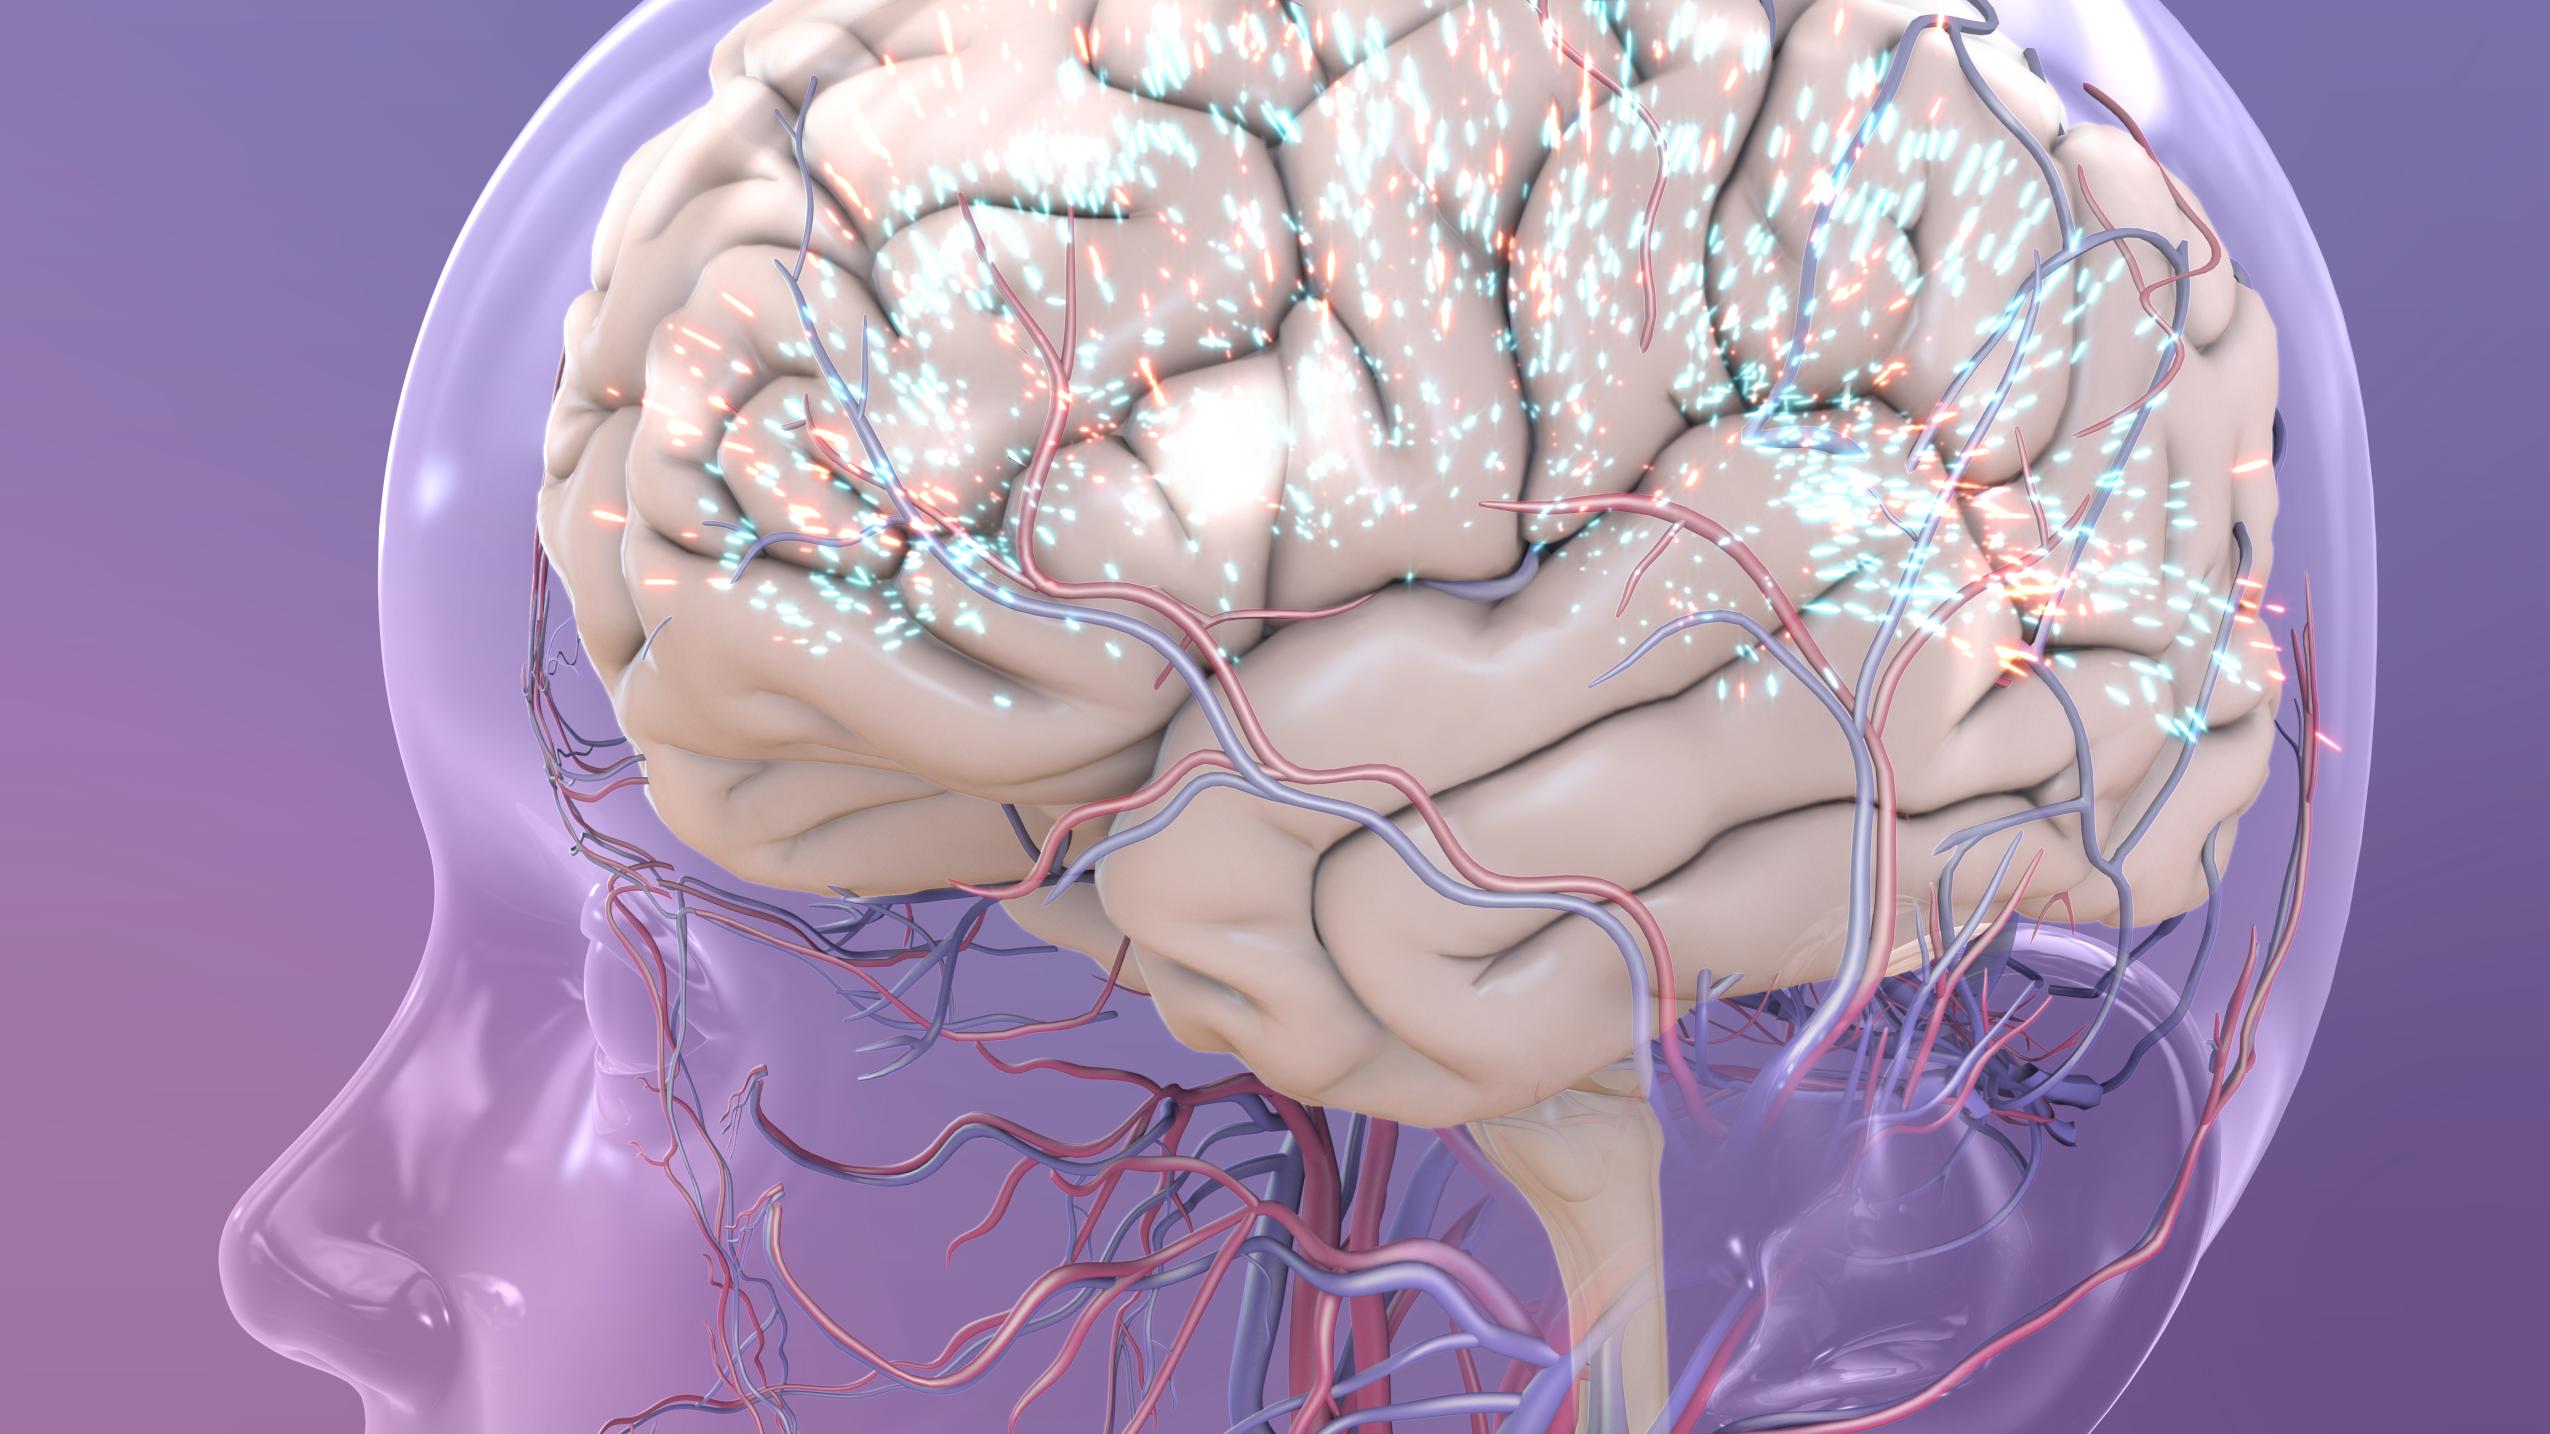

Изображения и визуализация внутренних органов человека